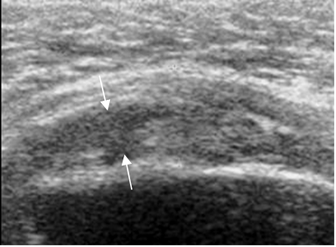

Fig 101. Ruptura parcial del supraespinoso.

Ecografía coronal. Area hipoecoica en el tendón, por ruptura parcial.